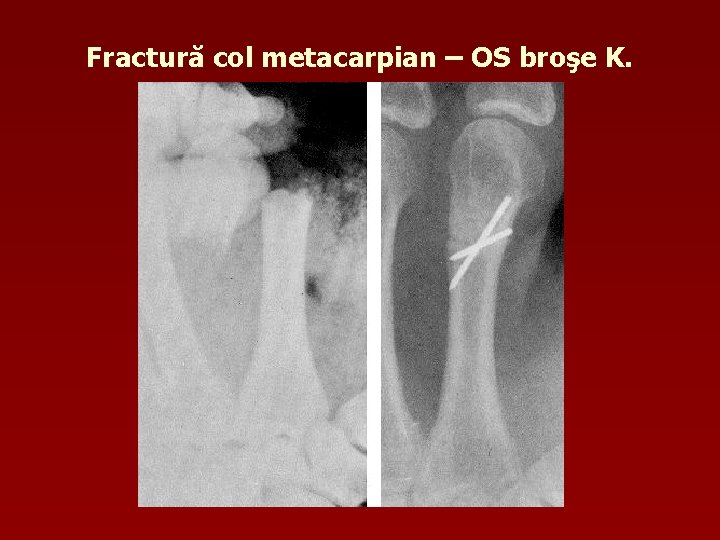

Fractură col metacarpian – OS broşe K.